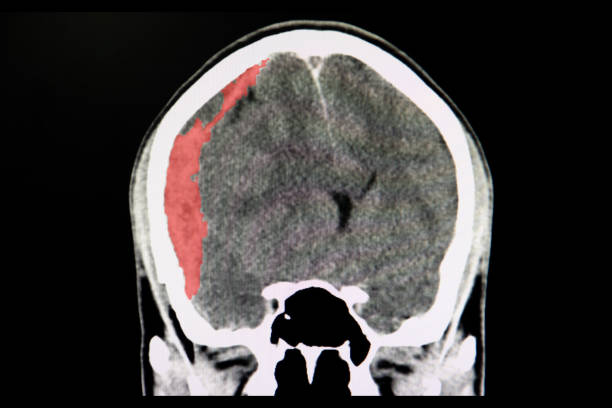

뇌출혈은 뇌안에 있는 혈관에서 출혈이 발생하여 뇌조직이 손상을 입는 질환이며, 중증의 뇌혈관질환 중 하나입니다. 일반적으로 고혈압, 동맥류, 혈관 기형, 혈전 등의 이유로 혈관이 파열하거나 뚫리면서 발생합니다.

고혈압은 뇌출혈을 일으키는 가장 일반적인 원인 중 하나입니다. 고혈압은 혈관벽을 약화시켜 혈관이 파열하기 쉽게 만들기 때문입니다. 또한, 혈관에 생긴 약간의 이상증상이나 동맥류, 혈관 기형 등도 뇌출혈의 원인이 될 수 있습니다.